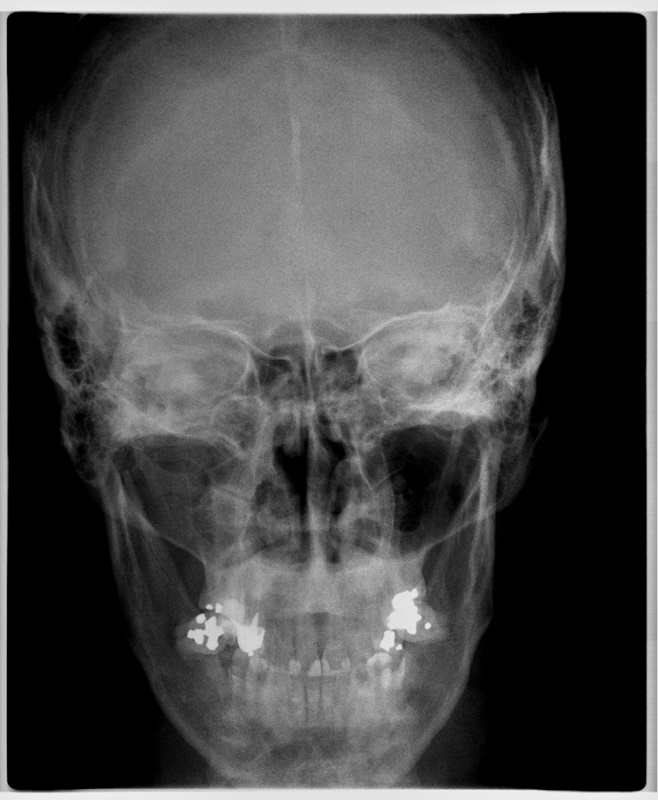

Seio Frontal (Póstero-Anterior FN)

- Utilizada para visualizar o seio frontal, as células etmoidais e as paredes da órbita.

- Avalia anormalidades de crescimento e assimetrias da maxila e da mandíbula.